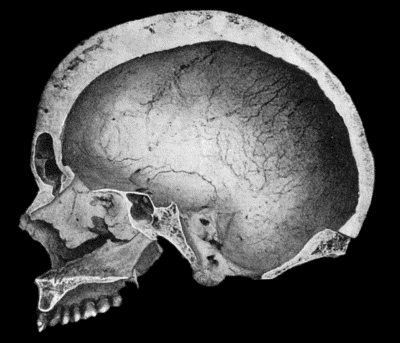

130.Syphilitic Disease of Skull 463

134.Changes in the Skull resulting from Ostitis Deformans 474